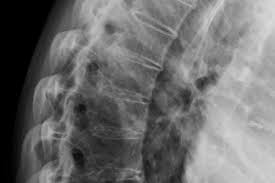

Auto immune disorder can affect any organ of body. In multiple sclerosis it attack nervous system, in Nephritic syndrome it affect kidney, In Ankolysing spondlitis the spinal vertebras, In Lupus it can affect sking, kidney, joints. In Ankolysing Spondylitis immune system attacks the spinal cord causing degeneration of spinal cord vertebral space.